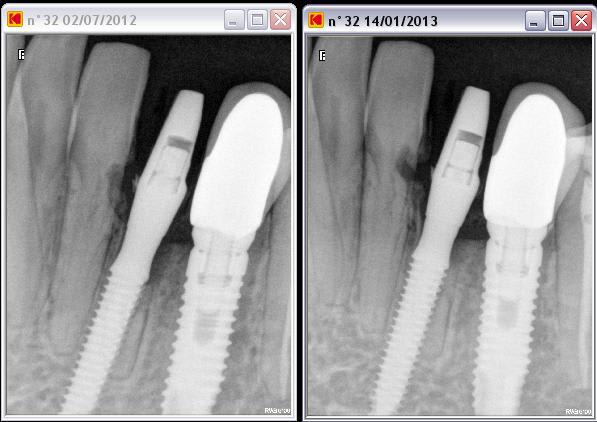

un petit cas qui a marché, mais sur lequel je n'aurai pas parié au départ...

32 dans un sale état on prévoit une EII, mais comme c'est une petite dent je decide de mettre un implant monobloc (dentium slimline fix type) et de faire la MFI

cependant petite surprise impossible de retirer la 32, j'ai donc décidé de passer à travers et de poser l'implant.

evidemment je ne faisais pas le fier et j'ai prévenu la patiente que tout pouvait arriver

mais parfois cela se passe bien et voilà ce que ça donne